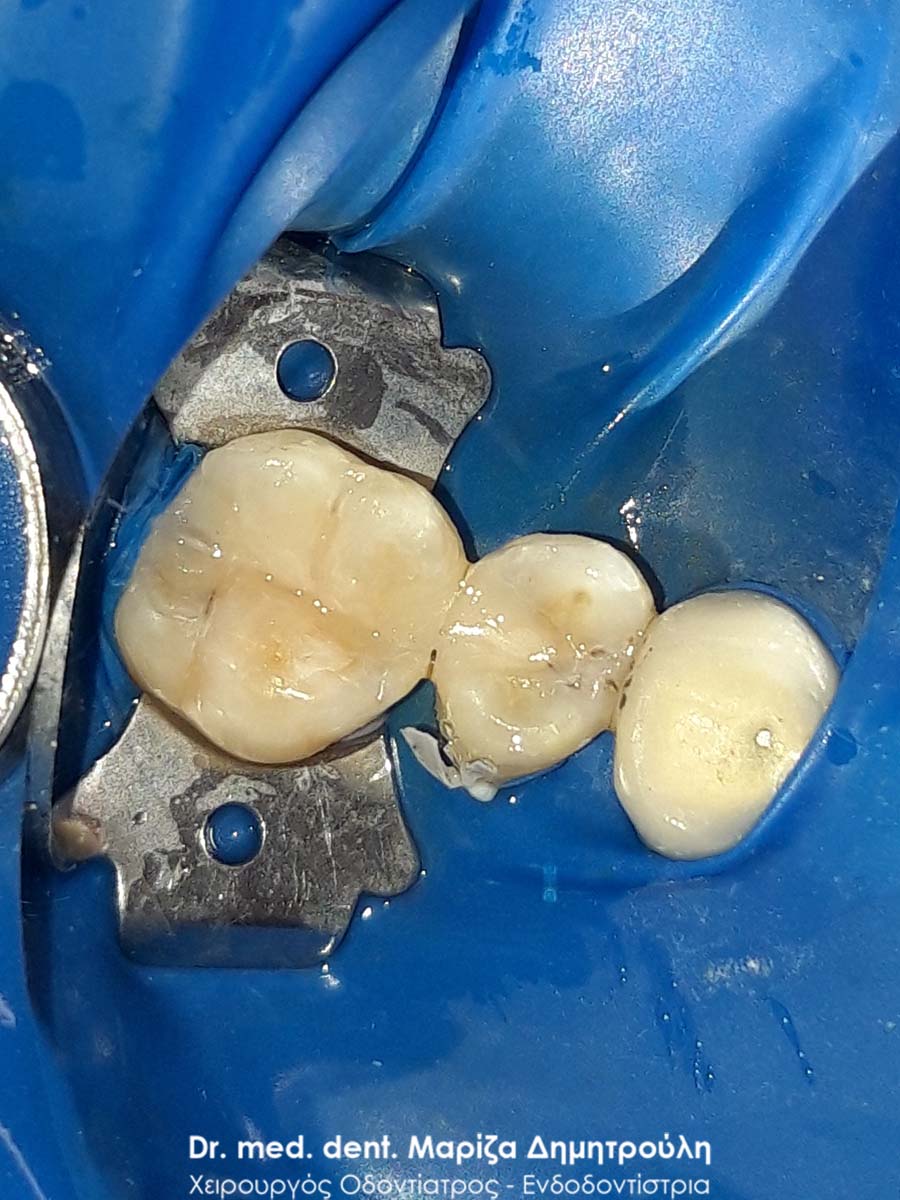

Περιστατικό – Αντικατάσταση σφραγισμάτων δοντιών

Ο ασθενής επιθυμούσε την αντικατάσταση των παλιών μαύρων σφραγισμάτων αμαλγάματος με λευκά σφραγίσματα σύνθετης ρητίνης.

Η θεραπεία πραγματοποιήθηκε με τη χρήση ελαστικού απομονωτήρα, όπως ορίζουν τα παγκόσμια πρωτόκολλα οδοντιατρικής για την αφαίρεση των μαύρων σφραγισμάτων. Οι οδοντίατροι θα ήταν καλό να χρησιμοποιούν απομονωτήτρα κατά την αφαίρεση σφραγισμάτων αμαλγάματος, έτσι ώστε ο ασθενής να εισπνέει ελάχιστα και να μην καταπίνει τον υδράργυρο, που απελευθερώνεται κατά τη διαδικασία αυτή.

Το σχέδιο θεραπείας του πρώτου γομφίου (δόντι με πολύ λευκό σφράγισμα) ήταν υπό συζήτηση, γι΄ αυτό και η αποκατάσταση του δοντιού με προσωρινό σφράγισμα.

ΠΡΙΝ

META